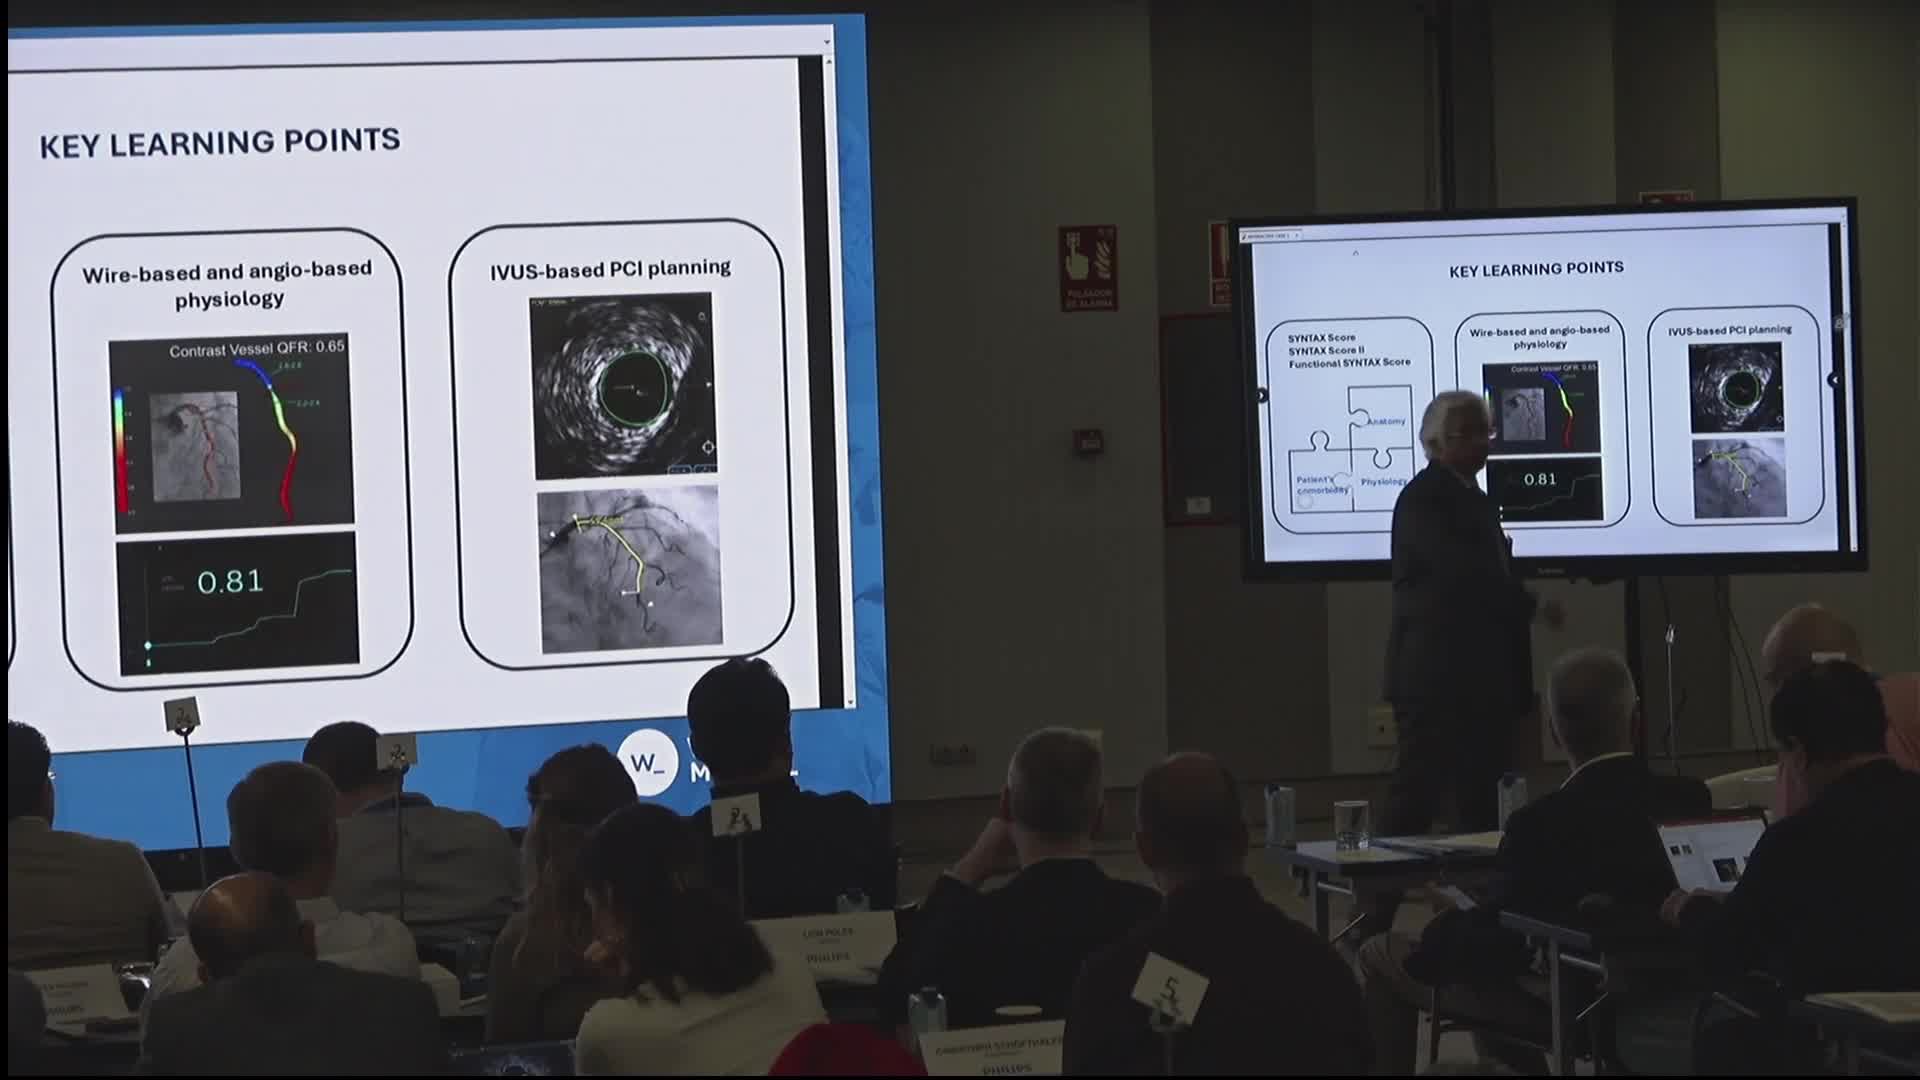

Advances in Co-registration, Coronary Physiology & Intra Coronary Imaging - April 2024 Day One

Advances in Co-registration, Coronary Physiology & Intra Coronary Imaging - April 2024 Day Two

Advances in Co-registration, Coronary Physiology & Intra Coronary Imaging - November 2023 Day One

Advances in Co-registration, Coronary Physiology & Intra Coronary Imaging - November 2023 Day Two

Advances in Co-registration, Coronary Physiology & Intra Coronary Imaging - November 2022 Day One

Advances in Co-registration, Coronary Physiology & Intra Coronary Imaging - November 2022 Day Two

Advances in Co-registration, Coronary Physiology & Intra Coronary Imaging - March 2022 Day One

Advances in Co-registration, Coronary Physiology & Intra Coronary Imaging - March 2022 Day Two